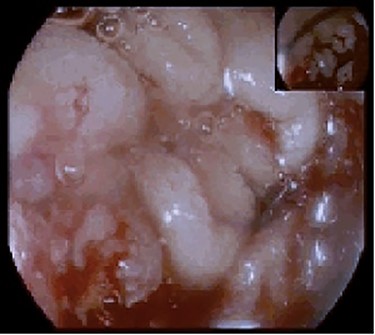

During the hospital stay, an imaging workup was carried out while awaiting the histological diagnosis and the patient had a thoracic, abdominal and pelvic CT done (Fig. 2A and B).

(A) Coronal cut of the abdomen on CT showing the third portion of the duodenum visibly thickened (arrow); (B) Arterial phase showing the circumferential involvement of D3 (arrow).

It described an almost circumferential thickening of the second and third duodenal portions consistent with the lesion described in the endoscopy, extended for 4 cm, with 12 mm of width, and several perilesional adenopathies, the largest measuring 9 mm.